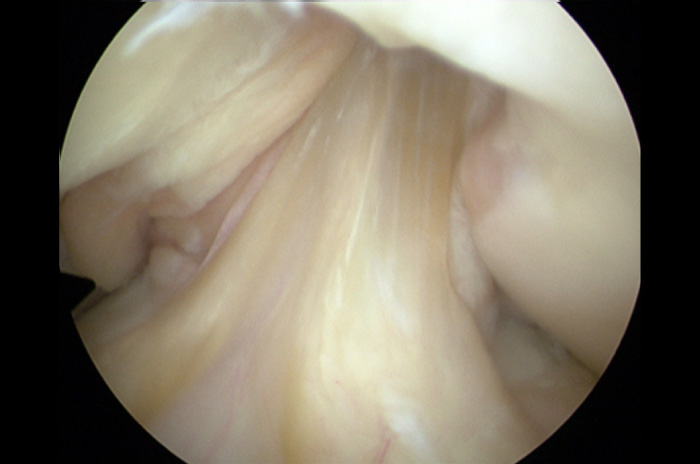

Con guías y brocas especiales se perforan túneles en la tibia y en el fémur, el injerto, es decir, el nuevo ligamento se coloca a través de estos túneles. La fijación de este nuevo ligamento se lleva al cabo con dispositivos especiales como el ACL TightRope® o el Endobutton® en el femur y en la tibia habitualmente con tornillos interferenciales (absorbibles, biocompuestos o metálicos).